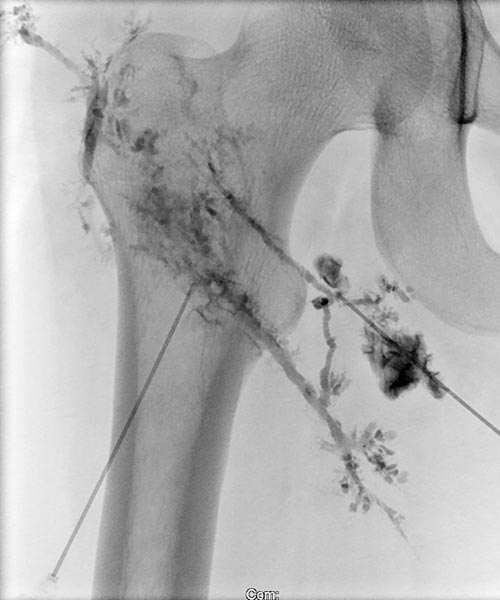

Direkte Lymphographie mit wasserlöslichem Kontrastmittel in Direktpunktionstechnik unter sonographischer Steuerung.

Es gelingt hier mehrfach die dysplastischen, erweiterten Lymphkanäle der LM im Subkutangewebe zu punktieren.

In diese wird dann das Picibanil (OK-432) als Sklerosierungsmittel injiziert um über die Entzündung die kutanen dysplastischen Lymphkanäle abzudichten.

Lymphographie in Direktpunktionstechnik unter sonographischer Steuerung.

Das subkutane Lymphgefäßsystem ist stark dysplastisch, zum Teil dilatiert und bizarr fuchsbauartig erweitert. Normale Lymphgefäße sind deutlich kleiner.

Auch hier wird Picibanil (OK-432) injiziert zur entzündungsinduzierten Lymphgefäßsklerosierung und Abdichtung der Haut.